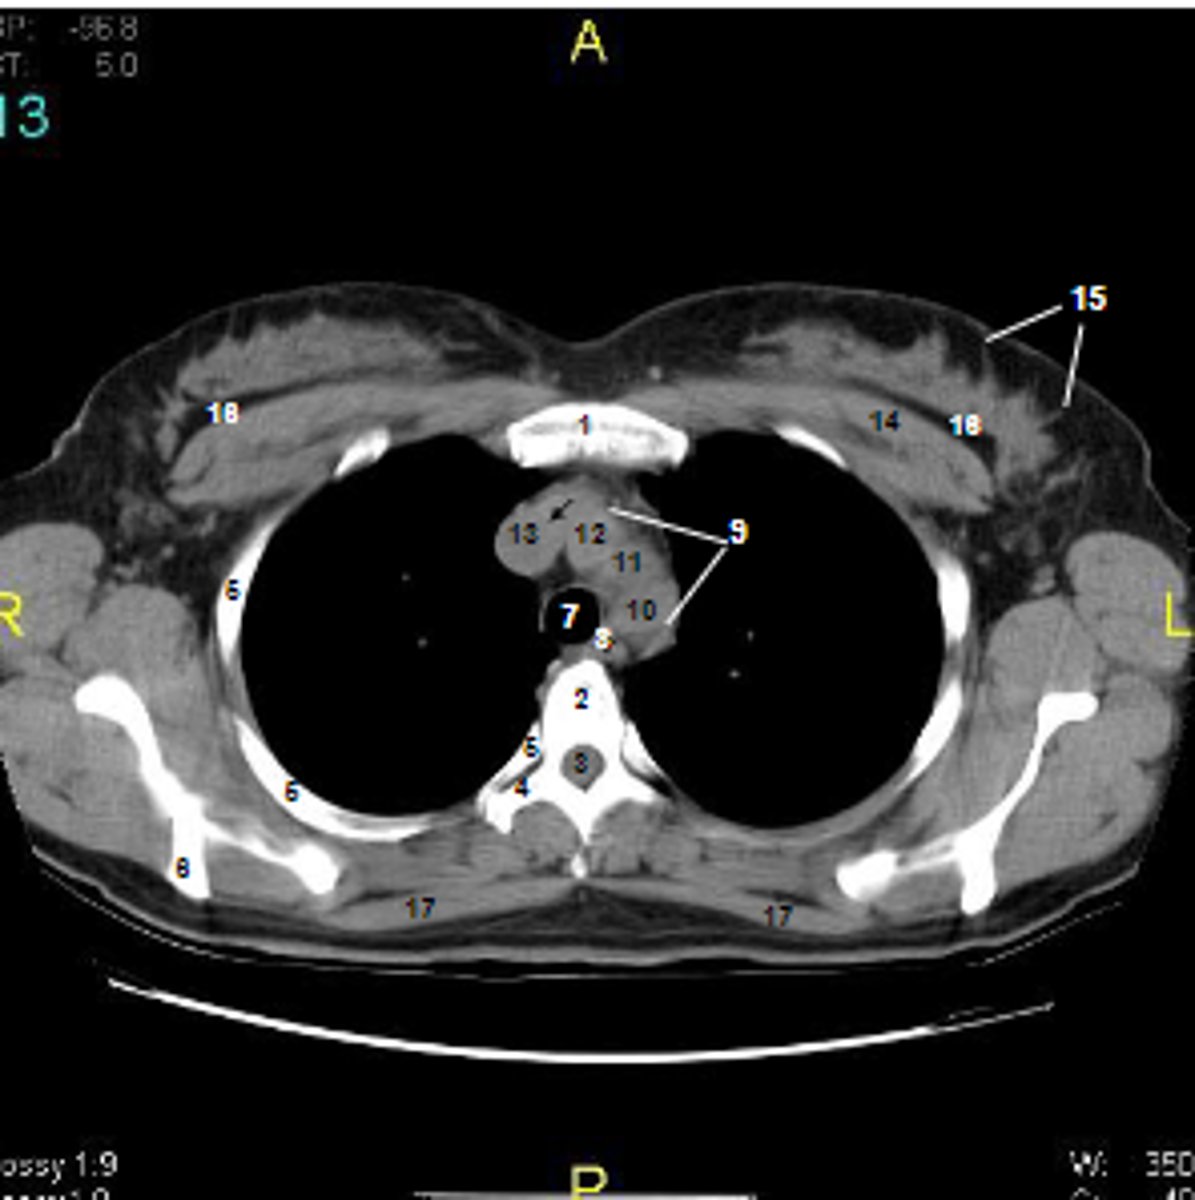

1

at what number is the sternum

2

at what number is the vertebral body

3

at what number is the vertebral canal/ spinal cord

4

at what number is the transverse process of vertebra

5

at what number is the rib

6

at what number is the spine of scapula

7

at what number is the trachea

8

at what number is the esophagus

9

at what number is the arch of aorta

10

at what number is the left subclavian artery

11

at what number is the common carotid artery

12

at what number is the brachiocephalic trunk

13

at what number is the superior vena cava

14

at what number is pectoralis major

15

at what number are Cooper's ligaments

16

at what number is the retromammary space

17

at what number is trapezius